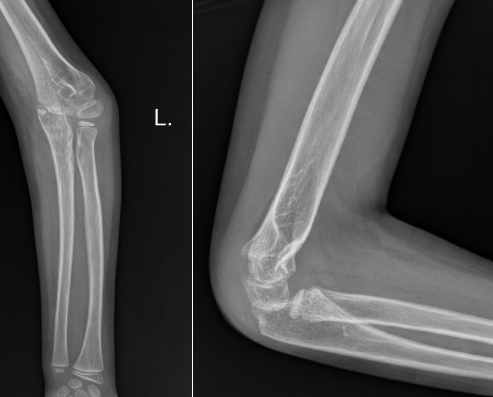

病例2:小红(化名)、女、9岁,3年前因摔伤致“左肱骨髁上骨折”,于当地诊所行手法复位夹板外固定,夹板固定一个月拆除外固定后逐渐发生左肘内翻畸形。

受伤当时的X线片

拆除夹板后的X线片

该例患者初始骨折为尺偏型肱骨髁上骨折,该种类型的骨折发生肘内翻畸形的可能性很大,需要在麻醉下手法复位纠正骨折端的尺偏移位,结合经皮克氏针固定,从而最大程度降低肘内翻畸形的发生率,但是当地诊所只是使用小夹板外固定,该固定不牢靠,骨折端容易再移位,且骨折端的尺偏移位纠正不足,种种原因引起了肘内翻畸形。针对该病例我们选择截骨矫形手术。